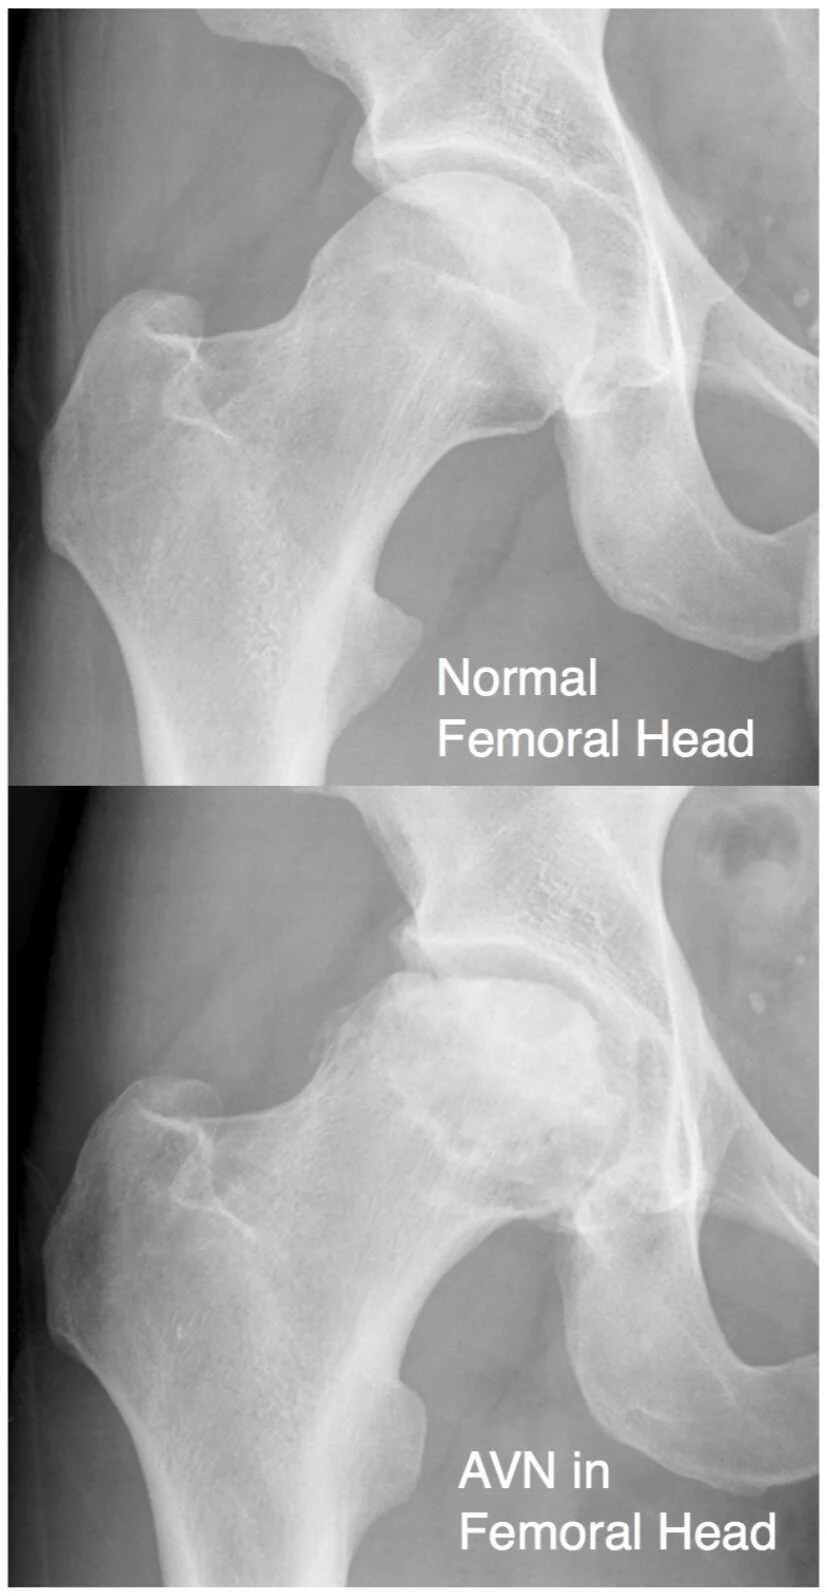

Avascular necrosis (AVN or osteonecrosis) of the hip is a painful condition that is caused by a disruption of the blood supply to the femoral head (top of the thigh bone).

Eventually, the bone dies off due to the lack of blood flow. This causes the joint end to loose its protective cartilage cap, and the joint surface becomes irregular. The surfaces are no longer smooth and free running, and this leads to stiffness and pain. Eventually, the joint wears away to such an extent that the bone upper end of the femur rubs on the acetabulum. This leads to arthritis.

X-rays

• X-ray is used to assess the joint for arthritis and the severity of AVN. Findings on the X-ray do not necessarily correlate with the severity of a patients symptoms.